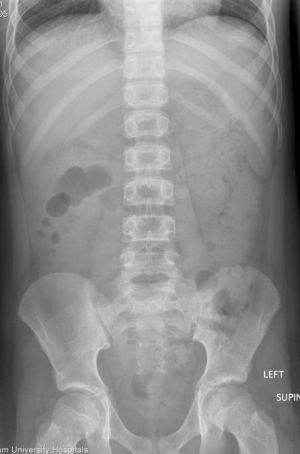

Hypovolemic Shock

- Hypovolemic